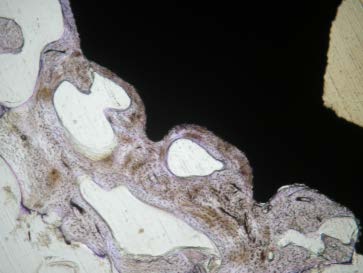

Material and Methodology a) Implant for use in ACIF made of glass-ceramics BAS-O (1996BAS-O ( -1999) ) In 1997 we used an implant made of bioactive glass-ceramics for ACIF in unstable injury to the lower cervical spine as an equivalent replacement of autologous bone drafts (Kokubo 1982,Urban 1992,Yamamuro 1995). It imitated bone tissue properties by its mechanical strength and bioactive properties. In vertical compression glass-ceramics exceeded twice the strength of cortical bone tissue and it was identical in bending strength. Disadvantage of BAS-O glass-ceramics is its fragility causing problems in optimizing the implant shape during biomechanical modelling. Based on mathematical studies we have retained the implant´s shape as a tapered prism with the following dimensions: length 15mm, height 7.8mm ventrally and 6.9mm dorsally, and width 13mm. Strength parameters of this shape exceeded the strength of an autograft (see Figure 1, Figure 2). Implant surfaces that face the vertebral bodies have small indentations of 1mm high. They are intended to secure a firm fixation immediately after the surgery before the fusion due to chemical bond occurs. During the insertion the implant had to be protected from a contact with the metal because of the risk of a damage. We used instruments covered with rubber for handling the implant.